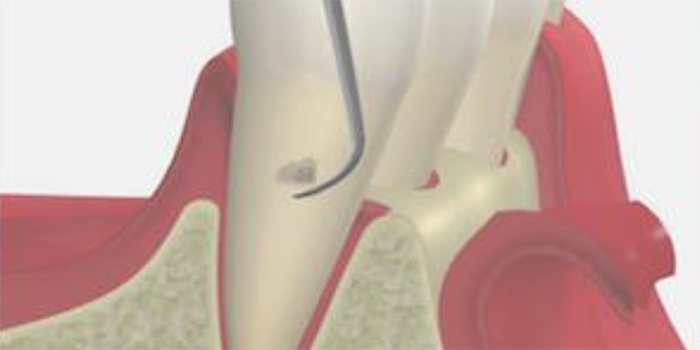

歯と歯茎の間の汚れをかき出すイメージイラスト

4. 歯周ポケット掻爬術

歯ぐきの内側の炎症をおこしている組織を取り除く処置です。

麻酔の効いている状態で行うため、治療中の痛みはほとんどありません。

内側からの炎症改善を目的としており、清潔になった歯の根に歯ぐきが付着し、汚れが溜まりにくい環境を作ることができます。

歯周ポケット掻爬術のイメージイラスト